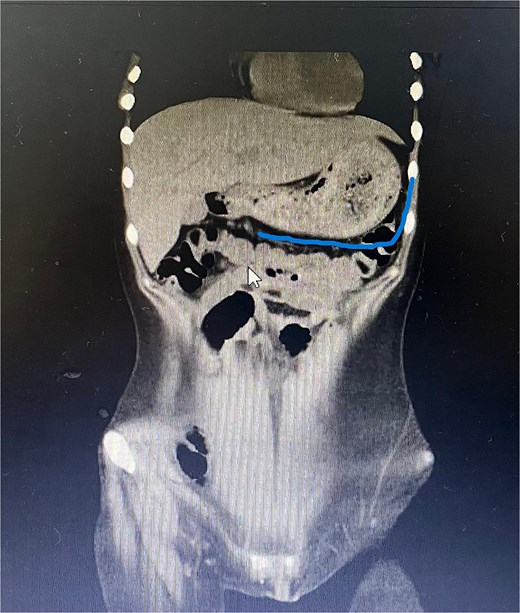

Twelve hours later, she was evaluated by the new emergency surgery team, who found a complete upper obstruction with a foreign body occupying the lower esophagus, the entire stomach, and the entire duodenum (Figs 1–3). A diagnostic laparoscopy (Fig. 10) with gastrotomy was performed (Figs 4 and 5), including foreign body removal (Figs 6 and 7), gastric repair (Fig. 8), and placement of a tubular drain. The findings revealed a large foreign body containing a significant amount of malodorous hair, measuring 30 cm long and 12 cm wide (Fig. 9). Large gauze pads were placed around the stomach to prevent contamination, and the bezoar was removed first through the duodenal area, as this was the area of smallest diameter and least compression. The gastric and esophageal portions were then removed. The foreign body was extracted transumbilically through a small 6 cm incision, protecting the abdominal wall with an isolation device. Gastric repair was performed using a 3–0 continuous suture polydioxanone (PDS) in a single layer. The cavity was irrigated with 3 l of saline solution. The operation was 2 h. Postoperative management included a nasogastric tube on gravity drainage, intravenous piperacillin/tazobactam 4.5 g every 6 h, intravenous tramadol 100 mg every 8 h for analgesia, and intravenous dimenhydrinate 50 mg every 8 h. The patient progressed favorably, with oral intake initiated on postoperative day 4. The tubular drain was removed on day 5 with minimal serous output. Psychiatry discovered that the patient had been diagnosed with trichotillomania in 2014 but refused pharmacological treatment. The patient confirmed that she has suffered from trichophagia since the age of 14. Pharmacological treatment with psychotropic medications and psychological support was initiated. On day 7, the patient was on a soft diet, without a nasogastric tube, with a white blood cell count of 10 740 cells/μl and 0% band neutrophils. Treatment with clomipramine was initiated. She was discharged that day and evaluated 7 days later with no problems.

Sagittal CT image showing the foreign body occupying the gastric cavity and extending into the third and fourth portions of the duodenum.

Sagittal CT image demonstrating the foreign body filling the entire gastric cavity.

Axial CT image showing the foreign body completely occupying the gastric lumen.